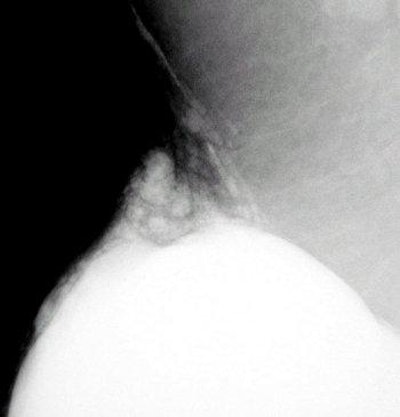

An extracapsular rupture of a silicone implant. Photo courtesy of Dr. Barbara Monsees.

"Contour abnormalities may be present and suggest rupture, but they are not specific to rupture," Monsees said. "Most implant ruptures go up and into the outer quadrants of the breast. So evaluate her and see how compressible she is. Take a single full view, including the implant, as a scout film and process it. Look at the film, and if there is silicone leaking, tell a radiologist and document it."